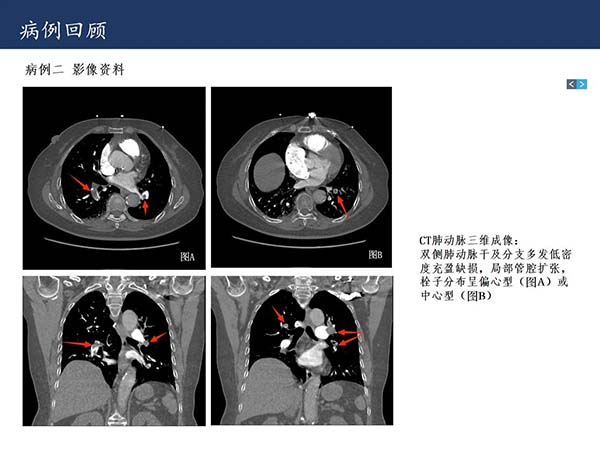

【杨柳病例】危急值病例:急性肺栓塞的影像表现